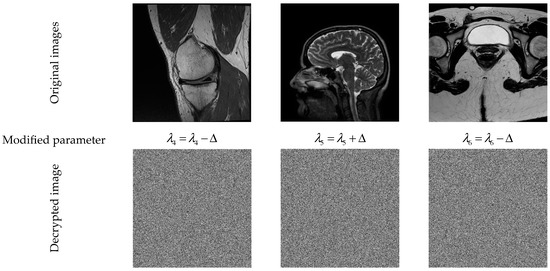

5.1. Sensitivity Analysis of the Secret Keys

- Define a security KEY to encrypt the first image in a dataset.

- Choose one (or more) parameter(s) of the KEY, and then increment the selected parameter by a small constant value (e.g., ) to generate a new security key (KEY*) that is used to encrypt the next image in the dataset, and so on. This strategy creates dynamic security keys, which prevents conventional attacks. For more information regarding this strategy, the reader is referred to [14,85].